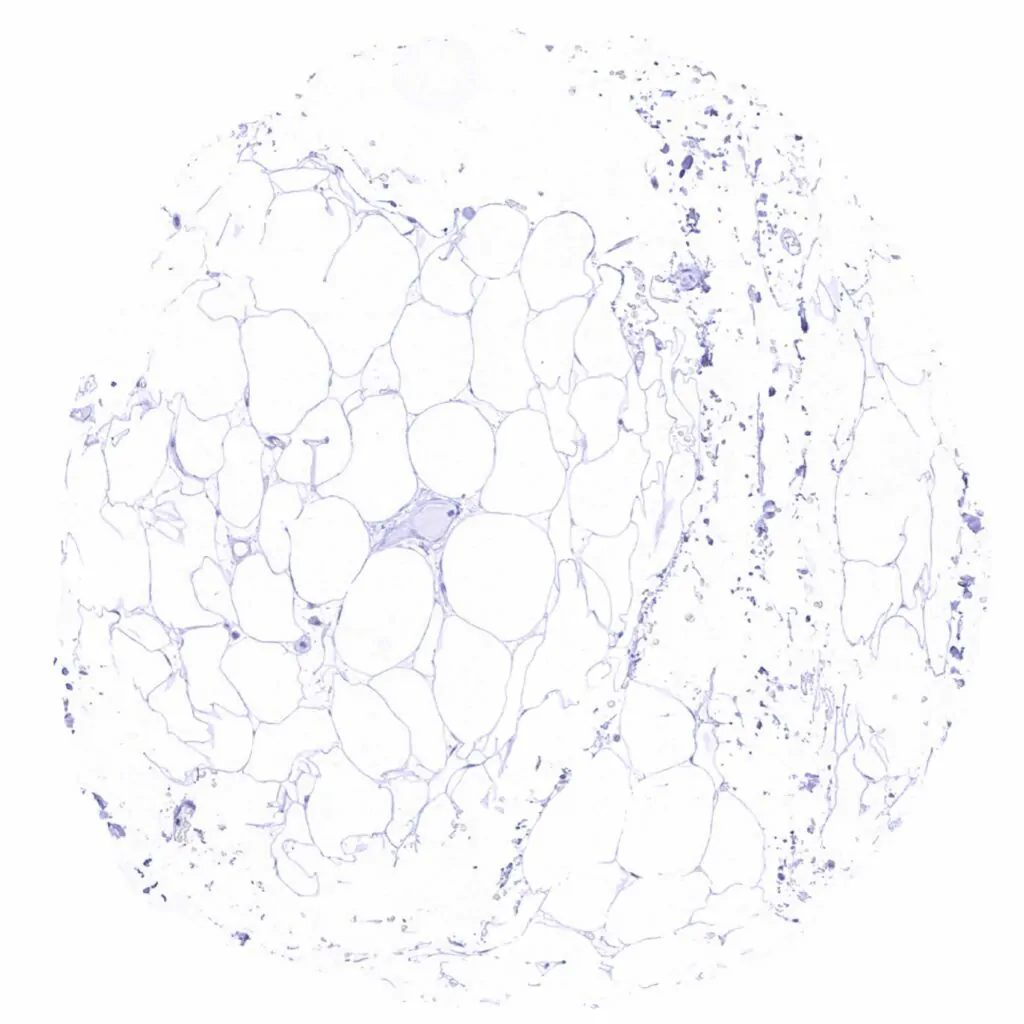

Fat